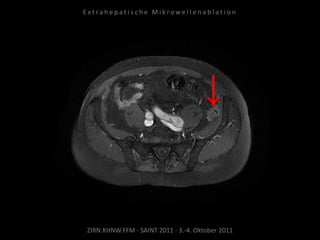

Kontrolle:

MRT 18.05.2010

MRT 01.07.2010

Das abladierte Tumorrezidiv zeigt keine

Vitalität. Jedoch neu aufgetretene

Tumormanifestation kranial im Bereich der

angrenzenden Samenbläschen.

Ablation des entsprechenden Areals

am 06.07.2010:

2 Nadelpositionen.

Erneut mit Kühlung von Harnleiter,

Harnblase und Rektum.